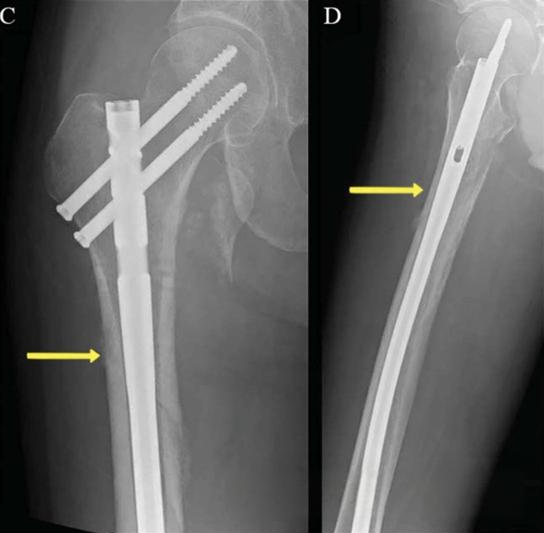

进针点扩髓对复位的影响

适当的进针点和适度的扩髓可以矫正成角畸形。进针点偏外导致内翻复位不良,在需要扩髓的髓内钉,转子下区与股骨近段相连的部分,如果扩髓不充分,可作为一种变形力(如下图)。外侧皮质会导致内翻畸形,内侧皮质则会导致外翻畸形。